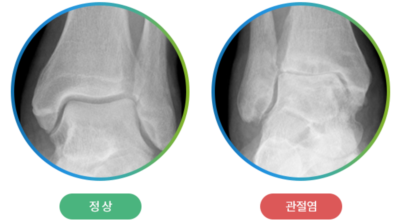

콘드로이틴을 말하는것으로 골 관절염의 관절 질환 치료에 글루코사민과 동반해 사용되는 물질의 성분입니다. 콘드로이친은 탄수화물의 한 종류로 연골 탄성섬유의 중요한 주물질입니다. 상어의 연골에 들어 있는 물질으로 신체의 관절, 연골, 피부에 적은 양으로 존재하는 물질이라고 알려져 있습니다. 콘드로이친은 연골의 파괴를 예방하고 새 연골 생성을 활성화하는데 많은 도움되는 것으로 알려져 있습니다.

글루코사민에 대조해 원료가 100배가량 비싼 고가의 원료인것으로 알려져 있답니다. 관절염 이유가 되는 것으로는 관절 연골이 닳아 없어지기 때문인데 퇴행성 질환이라고 하는 이유가 연골이 더 이상 생성되기 어렵기 때문이죠. 특히 콘드로이친이라 하는 성분이 나이가 들면서 길이가 짧아지고, 크기가 줄어들기 때문에 연골 구조가 변화되어 가면서 무릎뼈의 간격이 좁아져 통증을 유발하는 원인이 되는데 이 경우에 콘드로이친 효능을 바라볼 수 있답니다.